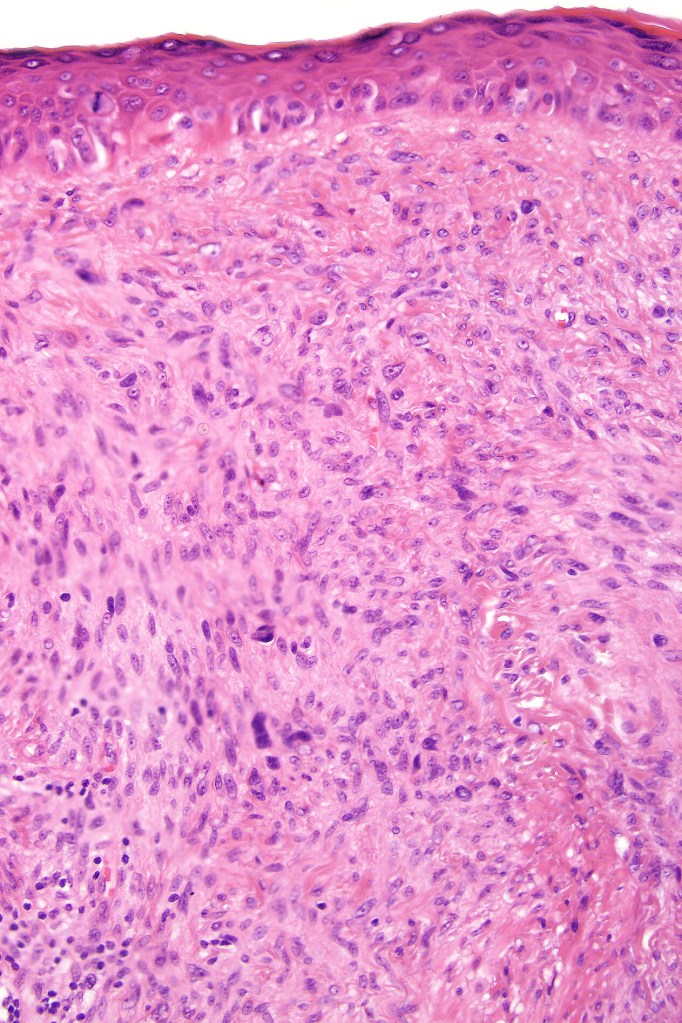

•Atypical melanocytes located predominantly along the basal layer of the epidermis, singly, in short arrays or extensively involving the whole epidermis

•Adnexal involvement

•Pagetoid spread

•Invasive tumor (lentigo maligna melanoma) typically characterized by a spindle cell population